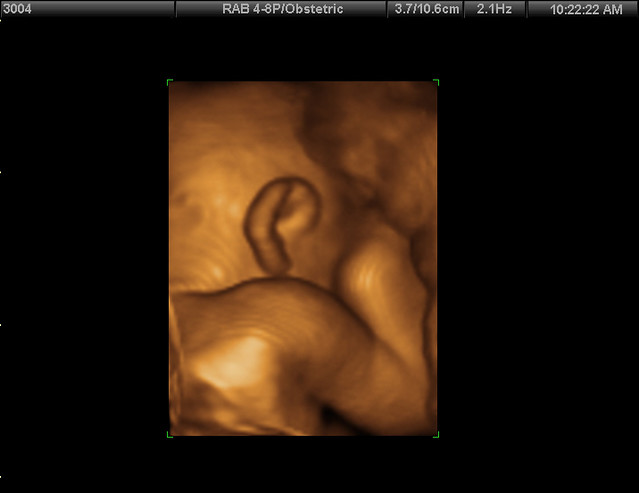

shoulder and an ear - Mrs. Flinger - FlickrLos Ultrasonidos 4D son una herramienta médica que permite tener una vista en tiempo real y tridimensional del feto durante el embarazo. Estos exámenes utilizan ondas sonoras para crear imágenes detalladas y realistas del bebé en el útero. No solo ayudan a los médicos a monitorear el desarrollo del feto y detectar cualquier problema de salud, sino que también ofrecen a los futuros padres una experiencia única y emocionante de ver a su bebé en movimiento antes de su nacimiento.